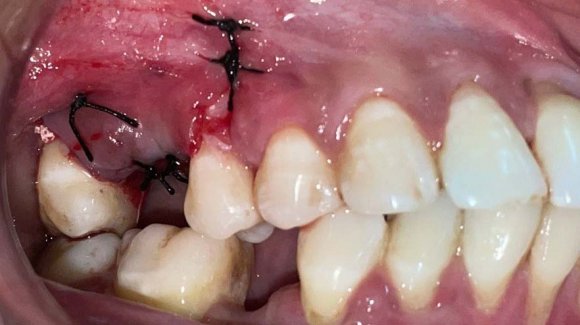

Un fil d'ostéosynthèse (de 4/10 ème de mm de diamètre) est ensuite inséré dans la perforation. Les deux brins seront toronnés et repliés au niveau de l'appareil d'orthodontie pendant le geste chirurgical afin de ne pas gêner le patient. La mise en traction par l'orthodontiste peut avoir lieu rapidement après la mise en place du système.

Les suites opératoires sont simples et le plus souvent résumées à celles de l'extraction des dents de sagesse quand elles ont lieu dans le même temps. Au bout de 6 mois de traction, le redressement incisif souhaité est obtenu et nous programmons l'intervention d'avancée mandibulaire.